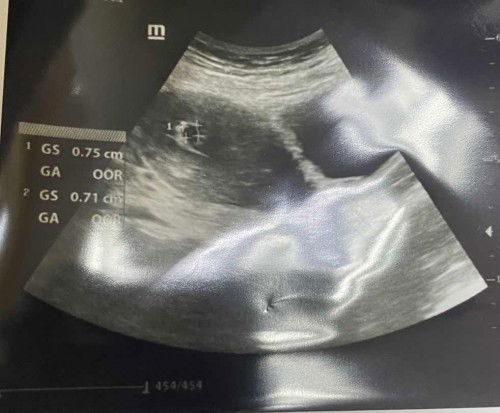

hi ibu2, nak tnya, last period sya 27/1/23, tpi period sya irregular.. klu follow trikh priod ptutnya skrg dah 11w, tpi bila scan dr ckp kecik sgt, xdpt detect usia janin. dr anggar less than 5w. bila ptut sya scan smula yer? sya dpt positif upt 01/04, n sya cek clear blue juga. skrg saya masi breastfeed anak 1st sya, ada kesan x utk kndungan sya? #pleasehelp